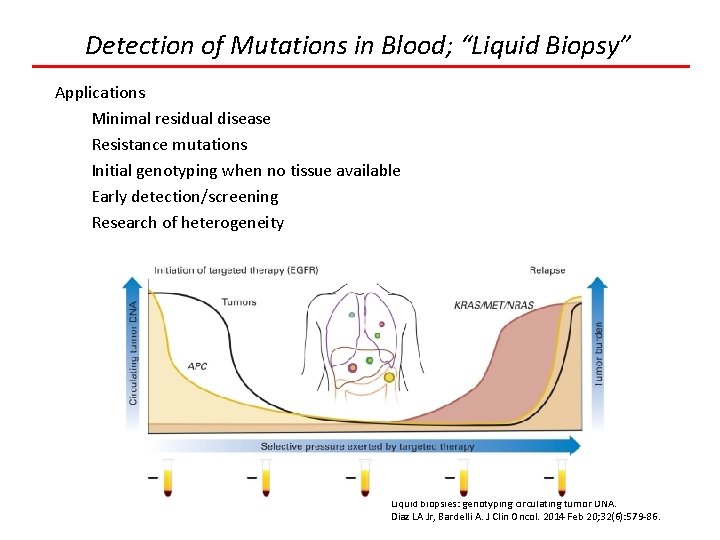

Detection of Mutations in Blood; “Liquid Biopsy” Liquid biopsies: genotyping circulating tumor DNA. Diaz LA Jr, Bardelli A. J Clin Oncol. 2014 Feb 20; 32(6): 579 -86.

Detection of Mutations in Blood; “Liquid Biopsy” Applications Minimal residual disease Resistance mutations Initial genotyping when no tissue available Early detection/screening Research of heterogeneity Liquid biopsies: genotyping circulating tumor DNA. Diaz LA Jr, Bardelli A. J Clin Oncol. 2014 Feb 20; 32(6): 579 -86.